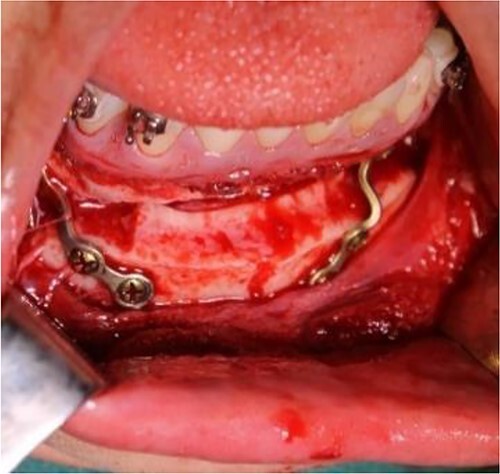

Figure 7.

Intraoperative clinical images: positioning and final fixation of the custom prosthesis with screws.

Figure 8.

Intraoperative clinical images: horizontal advancement genioplasty and plate fixation.